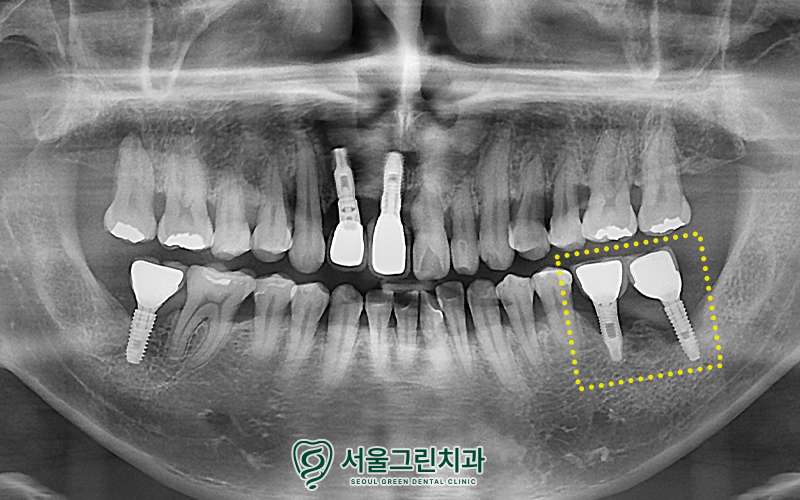

파노라마상에서

식립되어있는 임플란트 주변으로

잇몸뼈가 많이 녹아

까맣게 비춰보이는 모습을

확인할 수 있었습니다.

환자분께서 불편함을 호소하신 부위는

주변 잇몸 뼈 소실이 확인되어

제거 후 재식립을 계획하였고,

잇몸뼈가 부족하기에

재식립을 진행하면서

인공뼈 이식도 함께 진행하기로 설명드렸습니다.